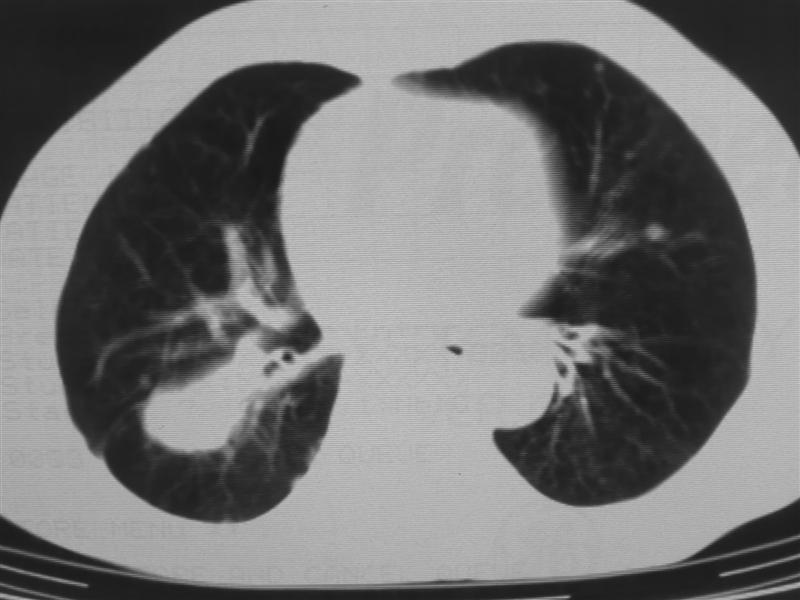

支持右下肺癌伴肺内转移

右下肺周围型肺癌伴双肺右侧叶间 胸膜及右肺门淋巴结转移

考虑:肺癌伴肺、胸膜 纵隔淋巴结转移可能性大!

肺癌伴肺、胸膜转移